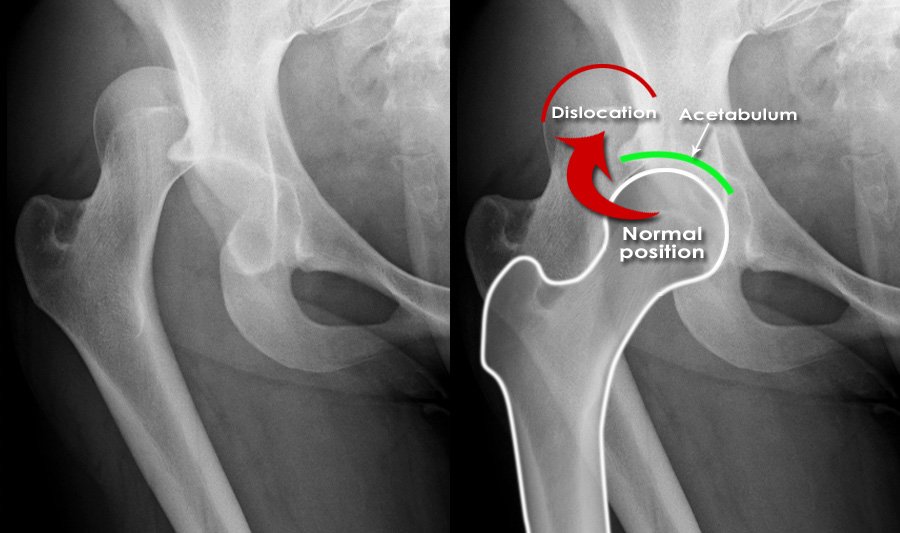

Hip fractures and dislocations are significant orthopaedic injuries that can severely impact your mobility and overall quality of life. A hip fracture occurs when a break develops in the upper part of the femur (thigh bone), often due to trauma, falls, or weakened bones from conditions like osteoporosis. A hip dislocation happens when the femoral head (the ball) is forced out of its socket in the pelvis, typically caused by high-impact trauma like car accidents or severe falls.

Both conditions require prompt medical attention. A hip fracture often necessitates surgery to realign or stabilise the bone, while a hip dislocation requires immediate reduction to restore the ball to the socket. Early treatment can prevent further damage, reduce the risk of complications, and support recovery.

• X-Rays: X-rays are used to identify fractures or dislocations in the hip joint. They also reveal the type and severity of the fracture.